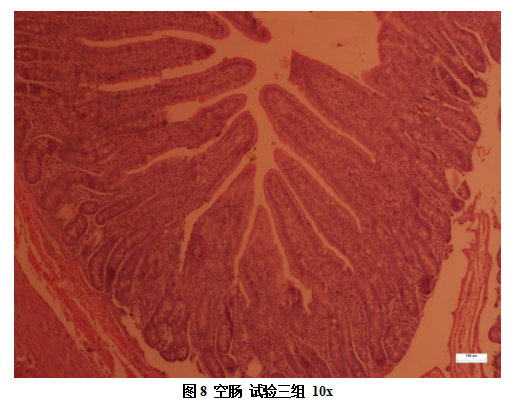

取十二指肠、空肠、回肠肠断进行固定,将固定的样品经冲刷、脱水、通明、浸蜡、包埋等处置后切片,进行苏木精-伊红染色,显微拍照,丈量绒毛长度及隐窝深度,推算绒毛长杜纂隐窝深度的比值,并推算绒毛高杜纂隐窝深度的比值(VH/CD,VCR),各指标取均匀数作为测定数据。